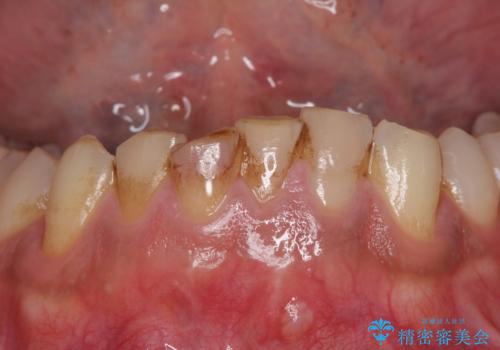

[前歯の変色] 前歯の見た目を改善したい

前歯が黒い セラミックで綺麗に 20代女性

前歯の見た目を改善したい